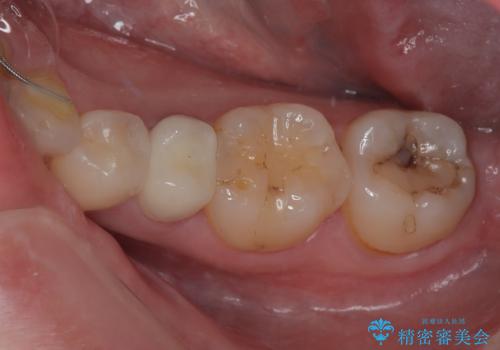

銀歯の下の虫歯を治したい オールセラミッククラウン・セラミックインレー修復